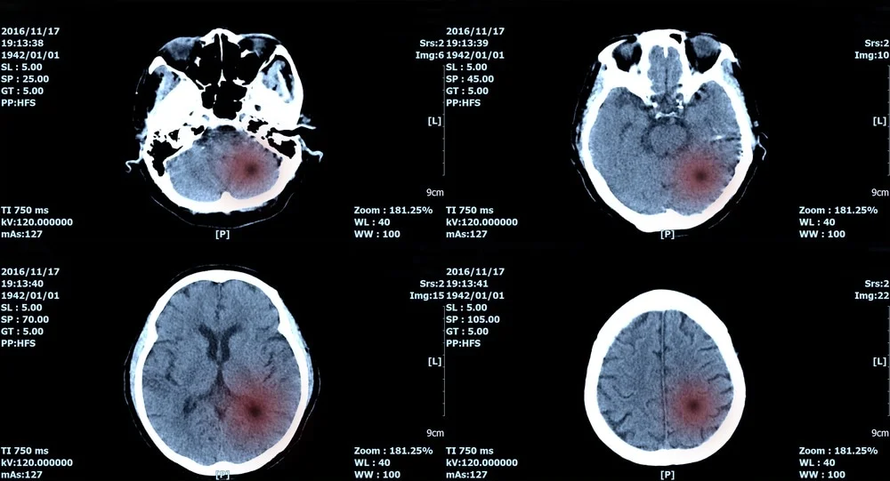

(Ngày Nay) -Ngày 28/2, Fujifilm và Trung tâm Ung thư quốc gia Nhật Bản công bố đã phát triển hệ thống trí tuệ nhân tạo (AI) có thể kiểm tra các khu vực nghi ngờ có khối u não ác tính từ hình ảnh chụp cộng hưởng từ - MRI.

Hệ thống được giới thiệu có khả năng cung cấp thông tin chính xác về kích thước của khối u giúp tăng hiệu quả điều trị.

Cụ thể, các nhà khoa học đã phát triển hệ thống AI chuyên biệt để phát hiện các khối u não ác tính, thường gọi là u thần kinh đệm (glioma). Đây là một loại ung thư hiếm gặp với số ít bệnh nhân và khi khối u phát triển có thể gây ra nhiều triệu chứng khác nhau, bao gồm đau đầu, buồn nôn và suy giảm ngôn ngữ.

Phương pháp điều trị điển hình cho căn bệnh này bao gồm chụp ảnh não MRI, thực hiện phẫu thuật để loại bỏ khối u, sau đó xạ trị và hóa trị. Hiện nay, việc sử dụng AI để quan sát các khối u ngày càng phổ biến nhưng do số lượng bệnh nhân mắc u thần kinh đệm ít nên dữ liệu lâm sàng khan hiếm và cho đến nay vẫn chưa có AI chuyên biệt để phân tích.

Hệ thống AI mới do Fujifilm và Trung tâm Ung thư quốc gia Nhật Bản hợp tác phát triển có thể xác định chính xác diện tích và kích thước của khối u thần kinh đệm, từ đó đưa ra phác đồ điều trị tối ưu cho bệnh nhân. Fujifilm đặt mục tiêu sẽ sớm cho ra mắt các sản phẩm được trang bị công nghệ AI phát triển chung này.